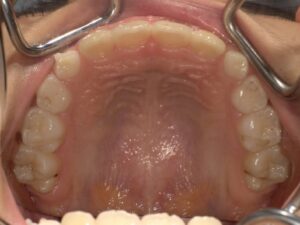

治療前(上顎咬合面)

治療後(上顎咬合面)

主訴:前歯の隙間と突出感が気になる

診断名:正中離開を伴う歯槽性上顎前突

治療区分:早期矯正治療(子供の矯正治療)

抜歯部位:非抜歯

使用装置:マウスピース型矯正装置(インビザラインファースト)

治療期間:約7カ月(動的治療期間)、永久歯への交換待ち

治療費:616,000円

起こりうるリスク:歯根吸収、歯肉退縮、知覚過敏、歯髄充血